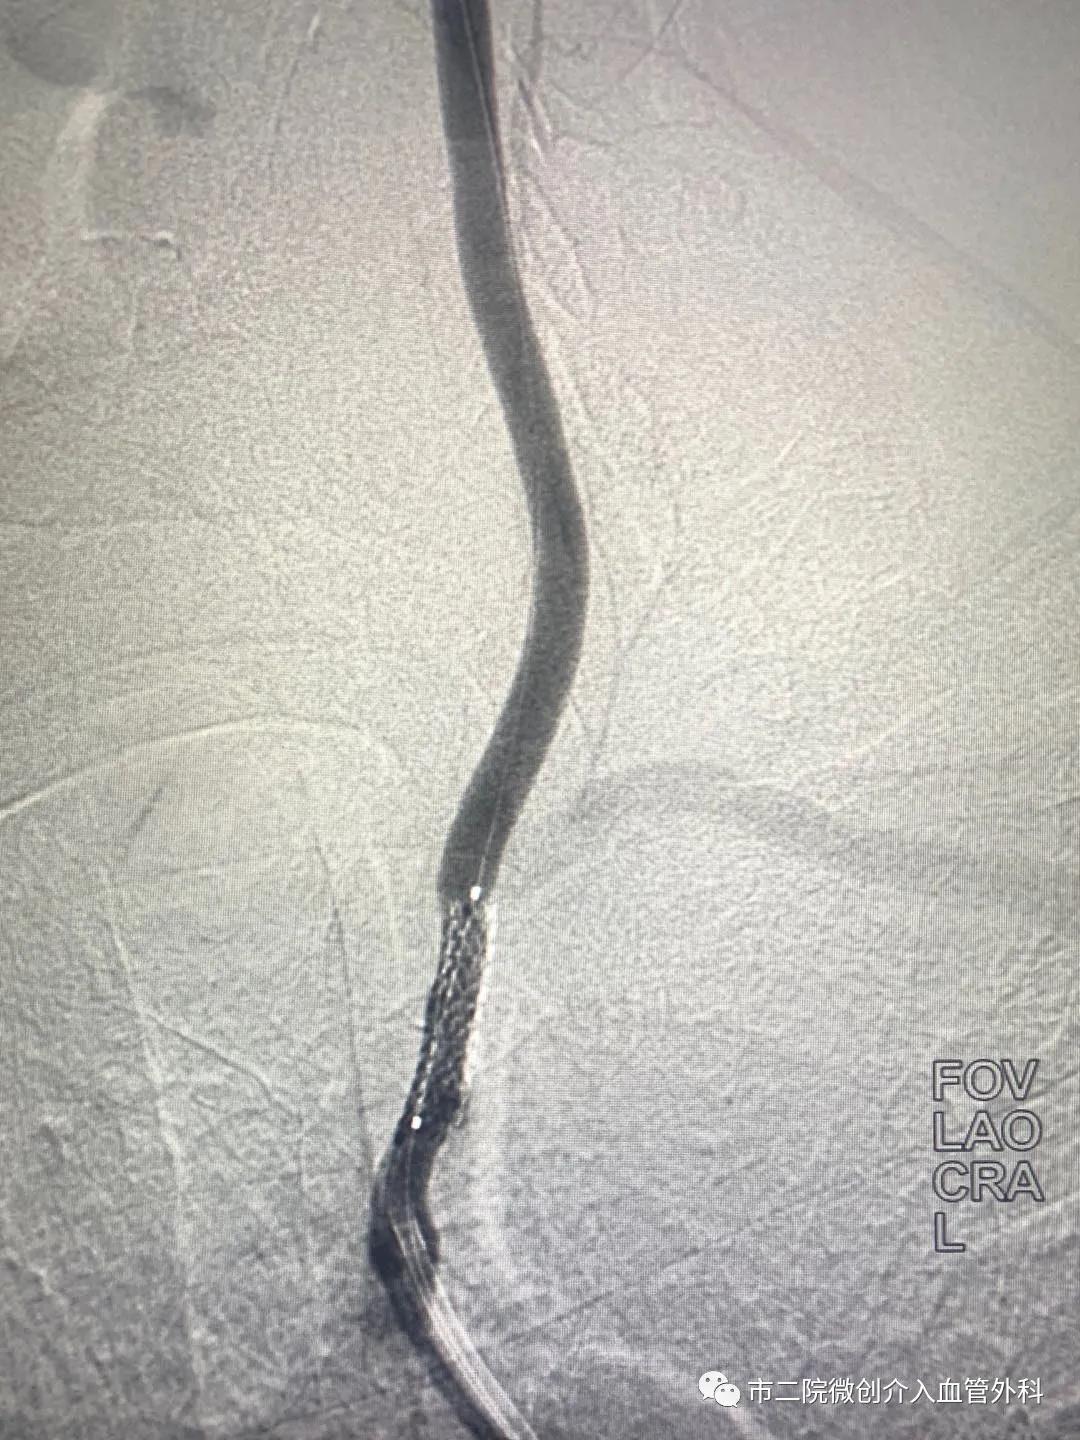

患者王某、男性、60岁以“发现左上肢脉搏、血压消失伴肢体麻木皮温减低”前来就诊。入院后完善相关检查,进行脑动脉造影,造影提示:左侧锁骨下动脉完全闭塞,左侧椎动脉重度狭窄。

术中利用导丝缓慢通过狭窄的左侧椎动脉引入球囊进行扩张,紧接着精准释放支架,再次造影椎动脉狭窄段消失,血流通畅,闭塞的左侧锁骨下动脉也开始有血流经过。一举两得,既解决了左侧椎动脉重度狭窄的问题,闭塞的锁骨下动脉也随之开通,患者各项生命体征平稳,手术顺利结束。

术前造影 术后造影